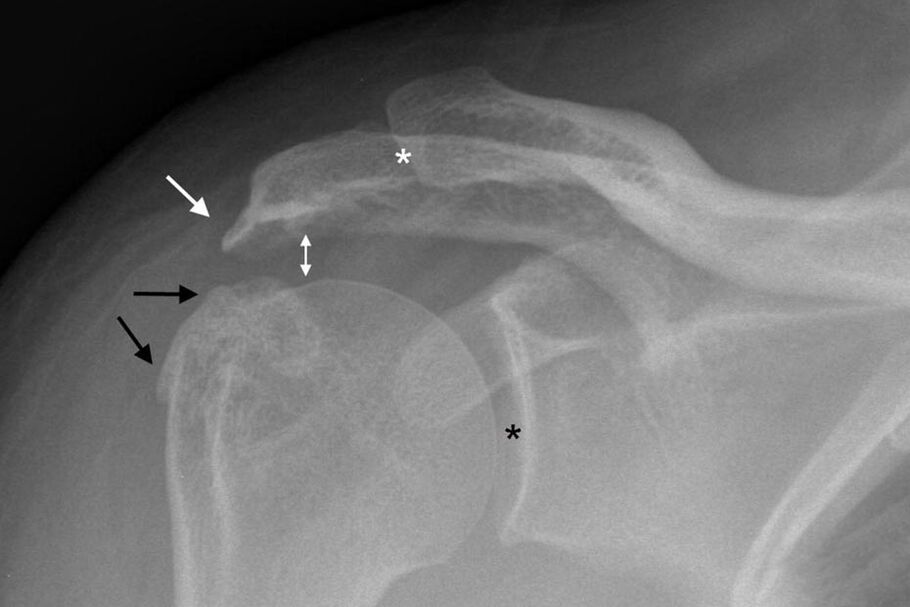

Osteoarthritis of the shoulder joint can be diagnosed by a standard x-ray of the shoulder.The picture is made in two projections.The doctor diagnoses the disease in the presence of factors such as:

- Narrowing of the joint space;

- Formation of osteophytes;

- Sclerosis of bone tissue.